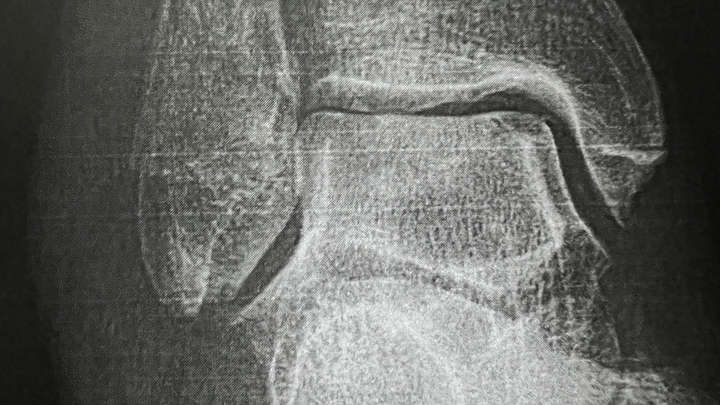

- Broke my ankle trying to be in shape.

- One month down & two to go in the cast.

- Next X-ray scheduled for end of December.